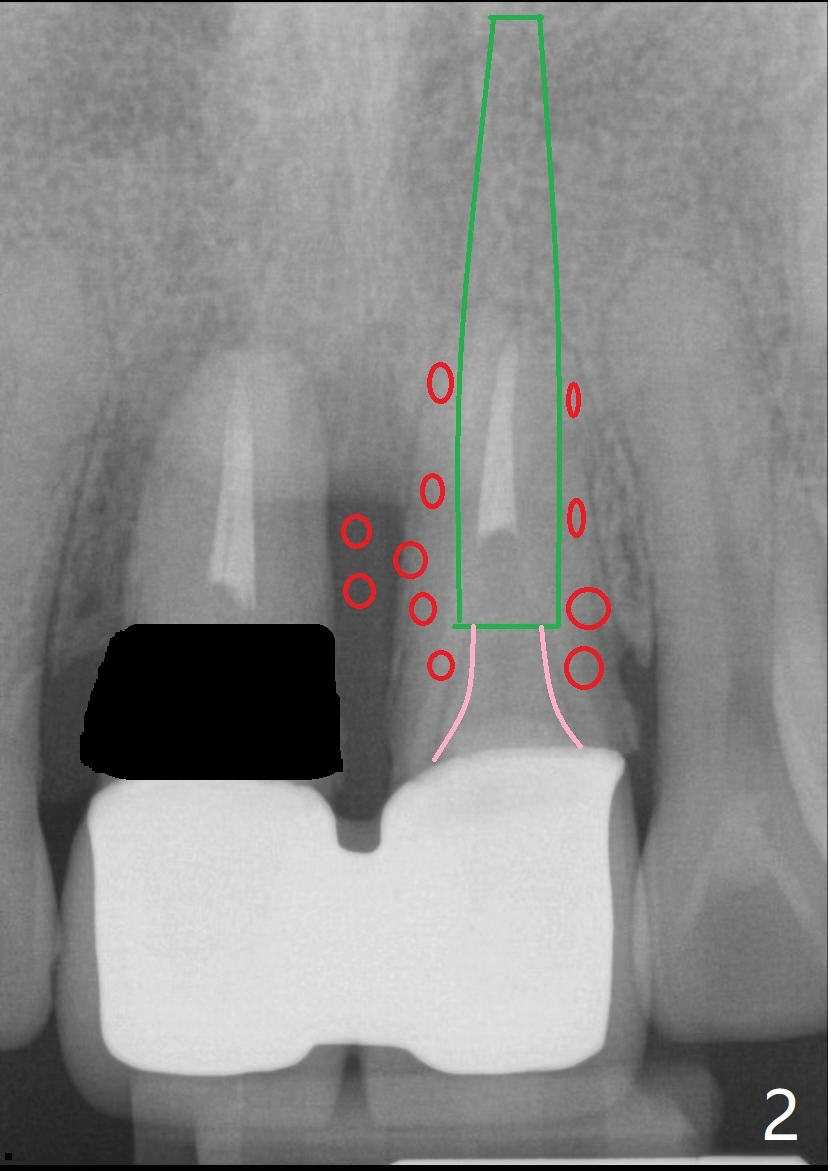

第一种方法,保留一个牙根(图二:例如8号牙),减少两个牙齿之间软硬组织萎缩,一个植牙(绿色,至鼻底),基台(粉红色),临时悬臂桥,植体周围以及龈乳头下植骨(红圆圈)。